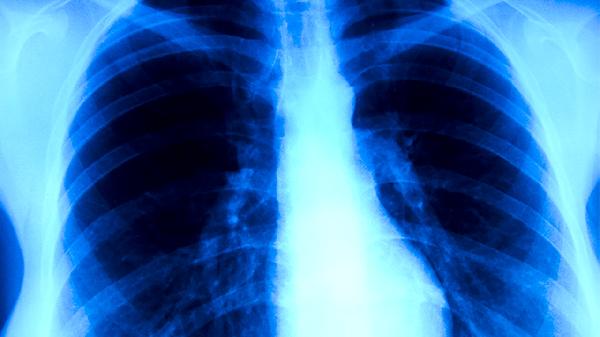

肺癌患者应定期复查胸部CT等影像学检查,在肿瘤科医生指导下制定个体化治疗方案。治疗期间需保持高蛋白饮食,适量补充维生素和矿物质,避免吸烟及接触二手烟。适当进行呼吸功能锻炼如腹式呼吸,有助于改善肺功能。出现咯血、持续发热等症状时需立即就医。